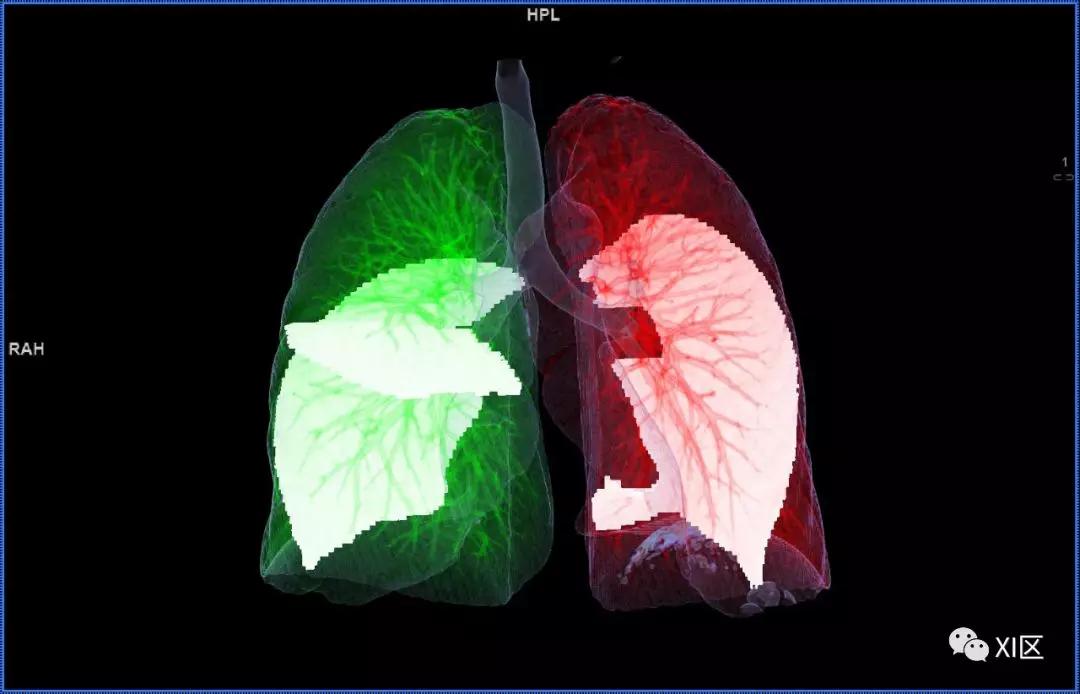

前后位,双侧位,后前位显示气道肺与胸部骨骼的关系

气管支气管树与两肺融合显示

肺表面重建显示叶间裂和肺的分叶

透视图显示肺的叶间裂和肺的分叶